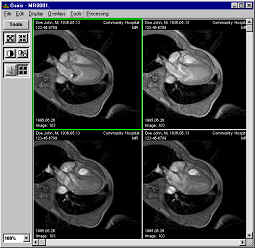

Pantalla de trabajo. Estudio DICOM abierto.

En la parte superior se muestran los datos del paciente, el clínico, fecha del estudio e institución donde se realizó dicho estudio.

En la parte central vemos la primera imagen que compone el estudio y, a la derecha, tres imágenes que se corresponden con los cortes axial, sagital y coronal, estos dos últimos reconstruidos a partir de las imágenes leídas, generalmente axiales. También se presenta cierta información técnica relativa a las imágenes, además de los valores de brillo y contraste y el porcentaje de zoom.

En la parte inferior se sitúan los controles y herramientas para manejar el estudio: botones de navegación por las imágenes, botón de animación (función "cine"), barras de control de los niveles de colores, un botón para cargar una paleta de color o un protocolo, controles de brillo y contraste, botones de zoom, un botón de inversión de la paleta, dos botones para aplicar filtros, un botón que permite restaurar los valores iniciales y un cuadro combinado en el que se pueden seleccionar las paletas o protocolos almacenados.